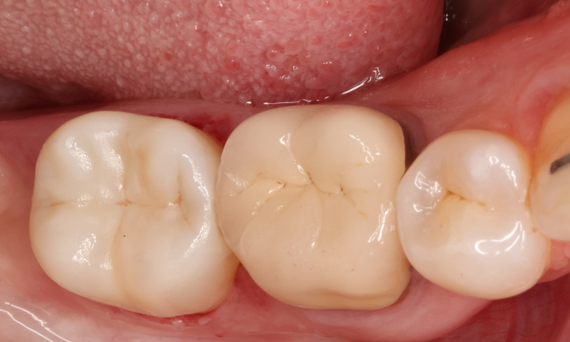

Lower second molar chairside restoration

A partial CEREC Tessera crown

A lower second molar with sensitivity presented with cracks as well as an extensive Class I composite restoration on the buccal surface. According to the minimally invasive concept a CAD/CAM partial crown was planned, fabricated and bonded using CEREC Tessera in a single visit.

Before: Failed amalgam restoration needing replacement. Patient complaining of sensitivity and tooth presenting multiple cracks.

After: Chairside CAD/CAM partial crown restoration fabricated with CEREC Tessera Advanced Lithium-Disilicate glass ceramic.

Dr. Carlos Eduardo Sabrosa

Rio de Janeiro, Brasil